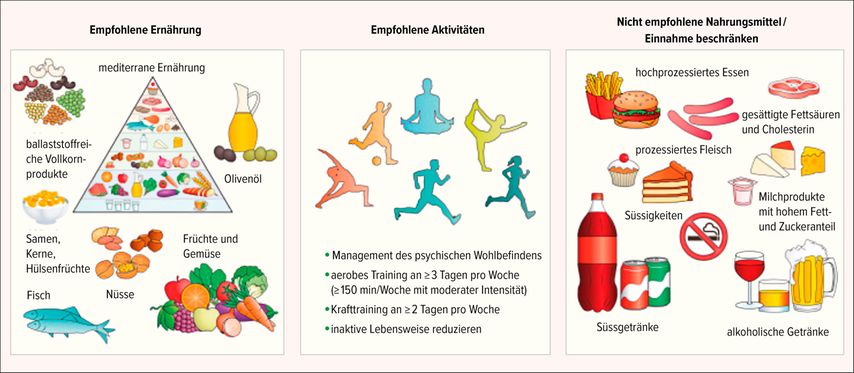

Vor allem Fruktose und Sukrose scheinen zur Entstehung von MASLD beizutragen: In einer Studie des Universitätsspitals Zürich zeigten gesunde Probandinnen und Probanden nach nur sieben Wochen, während denen sie täglich mit Sukrose oder Fruktose gesüsste Getränke tranken, eine De-novo-Lipogenese in der Leber. Diese wurde allerdings nicht beobachtet, wenn die Getränke mit Glukose versetzt wurden.15 «Änderungen des Lebensstils und der Ernährung sind daher nicht nur ein Bestandteil in der Behandlung von MASLD, sondern auch eine wichtige Prophylaxe», sagte Semela. Er verwies dabei auf einen von Patientenorganisationen, Wissenschaftlerinnen und Ärzten gemeinsam entwickelten Patientenleitfaden (Abb. 1). Dieser soll Patientinnen und Patienten dabei helfen, fundierte Entscheidungen in der Behandlung von MASLD zu treffen.16

Abb. 1: Lebensstil und Ernährung – Empfehlungen für Patientinnen und Patienten mit MASLD (modifiziert nach Francque SM et al. 2021)16